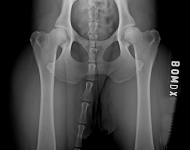

BOM LÜW 2 a

BOM LÜW 2 b

BOM LÜW 2 c